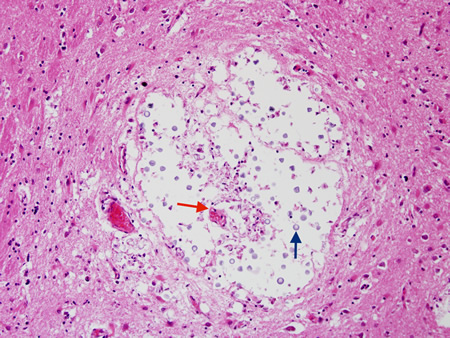

Biópsia de gânglios da base de paciente com meningoencefalite criptocócica exibindo expansão criptocócica (seta azul) de espaços de Virchow-Robbin em volta de um vaso lenticuloestriado (seta vermelha)

Do acervo pessoal de Robert E. Schmidt; usado com permissão